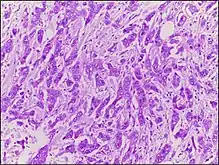

Micrograph of breast tissue with ductal carcinoma. H&E stain.

Ductal carcinoma is a type of tumor that primarily presents in the ducts of a gland.[1]